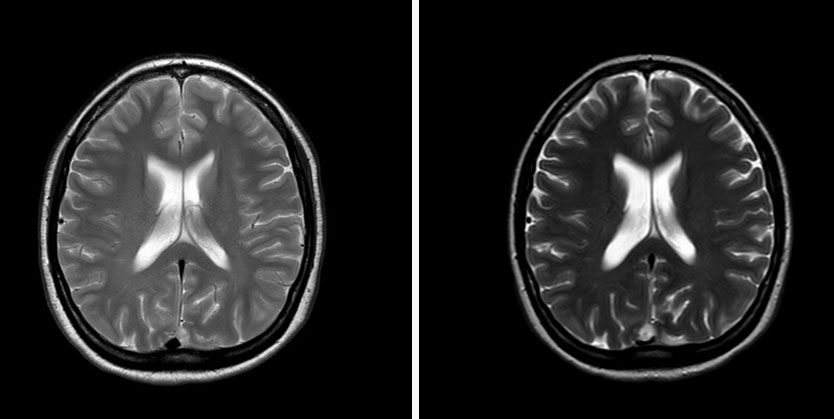

Magnetic resonance imaging (MRI, Figure 1A and Figure 1 B) revealed a small lesion in relation to the posterior third of the superior sagittal sinus, with a size of 12 × 10 × 10 mm, hyperintense in T2 and FLAIR sequences and hypointense in T1. The lesion showed homogeneous enhancement after Gadolinium administration, all suggestive of meningioma given the radiological findings. Superior sagittal sinus invasion and moderate stenosis by the meningioma were observed (Figure 2). On the other hand, no optic nerve sheath or Meckel cavum anomalies were observed. There was no suggestion for idiopathic or benign intracranial hypertension.

Figure 5: Gadolinium-enhanced T1 MRI in axial section. Left side corresponds with the first MRI and right side with the MRI after six months. We can observe meningioma stability with partial re-expansion of the superior sagittal sinus in the posterior third comparing both studies.

Share Image: